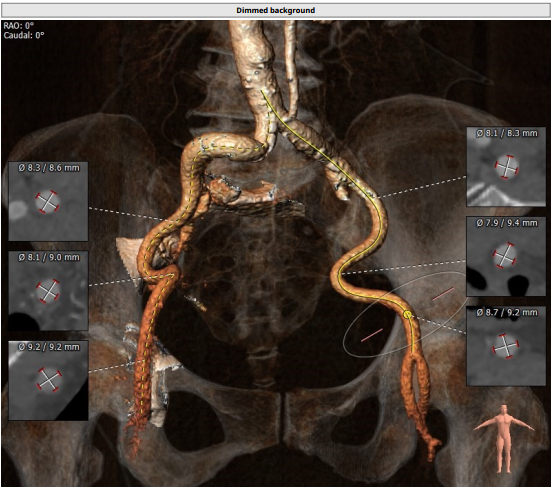

入路情况较为特殊,右股入路扭曲,左股尚可,腹主迂曲,上大鞘和过输送器时应轻柔,以防止血管并发症。决定左股作为主入路,左桡作为辅路。弓部呈锐角,过弓时应注意血管损伤,必要时借助抓捕器。